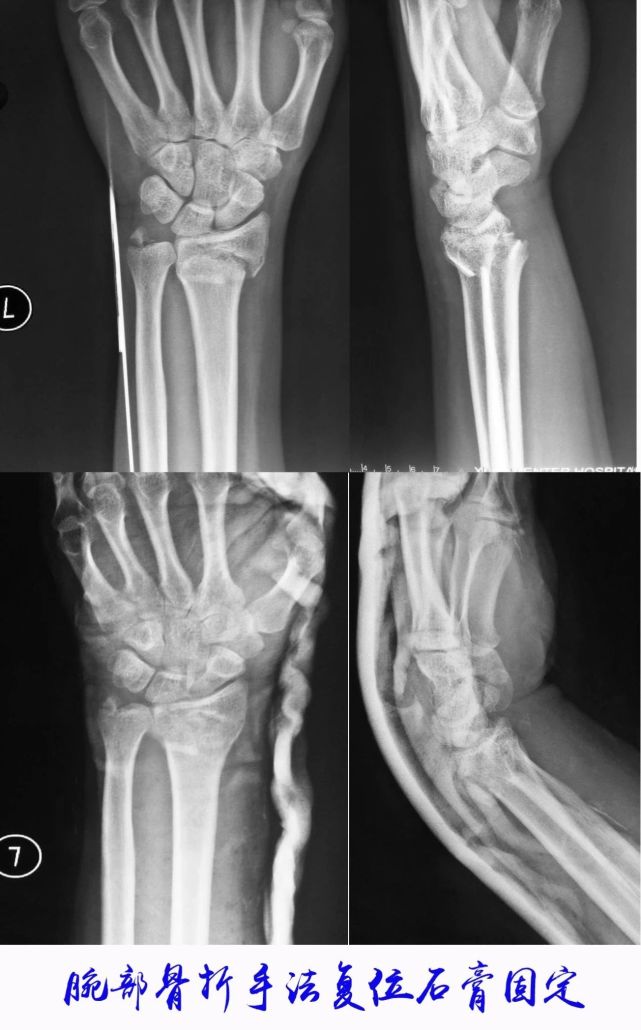

我院骨科继承了70余年野战医院的光荣传统,在积累了各类创伤、骨病、骨肿瘤等疾病治疗丰富经验的基础上,我

所属医院:西安唐城医院 我院骨科继承了70余年野战医院的光荣传统,在积累了各类创伤、骨病、骨肿瘤等疾病

西安市红十字会医院创伤骨科分为创伤骨科一病区、创伤骨科二病区。2008年主持的科研课题“外伤性骨髓炎的

创伤骨科:自1911年成立“红十字西北战地医疗救护队”以来,骨科创伤治疗就创伤骨科科研成果丰硕,其中《带